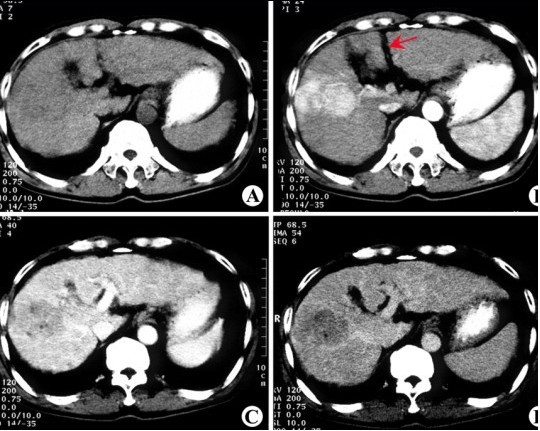

前言:2013年8月初,魏某在单位体检发现是肝癌,弥漫型,最大肿块3×4cm,门静脉有瘤栓,肝功能正常。于8月中旬和9月初各介入治疗一次,9月6日肝内肿瘤最大占位达9.6×7.3cm,10月中下旬出现腹胀,腹水。曾到多家医院就诊,服用多种药物,效果都不佳。

CT检查 原发性肝癌

效果:经过两个疗程结束后复查,CT示瘤体明显缩小,腹水大量减少,但并未消失。现疼痛症状有所缓解,食欲增强,体重略有增加,精神状况也有所好转。